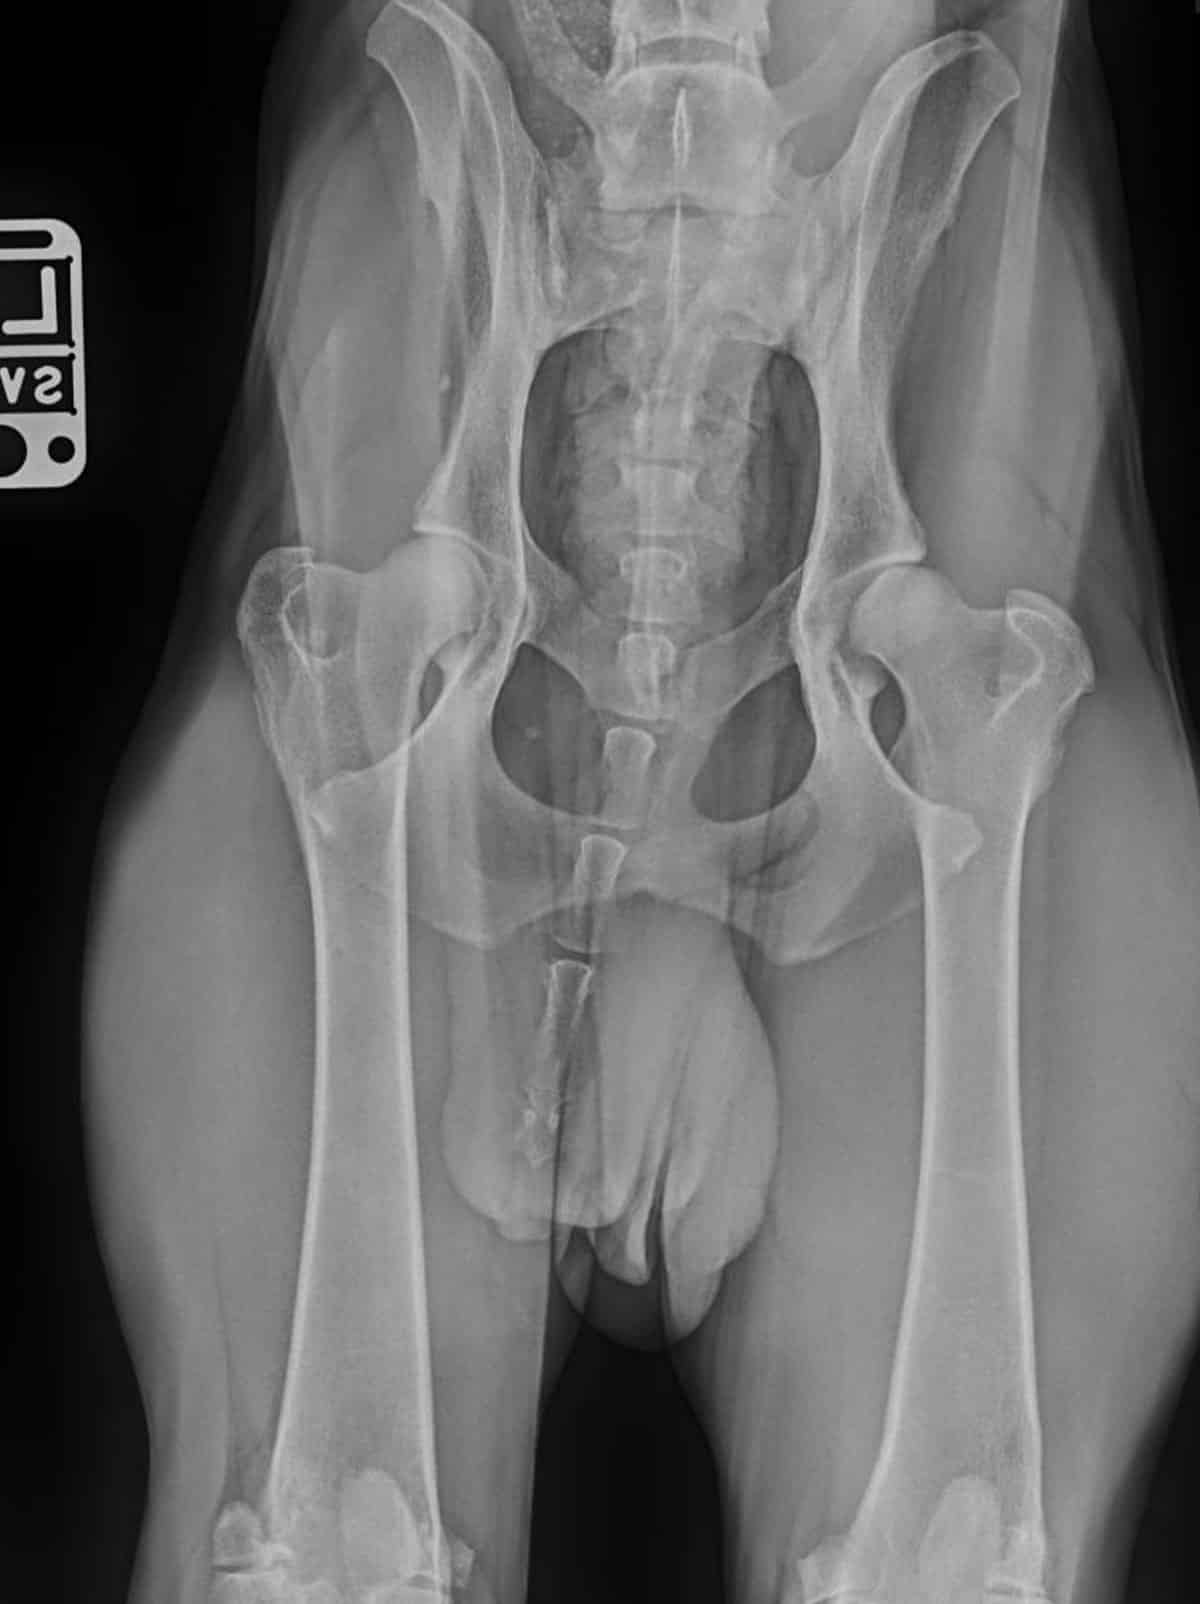

- Evaluation for broken bones or trauma

- Evaluation for bone and joint disease including arthritis

- OFA Certification

Radiology is one of the most common diagnostic modalities we use in the clinic. Radiology gives us a rapid and relatively non-invasive look inside the body from head to tail. Radiographs help us assess not only the skeleton of the pet but also the organs within the chest and abdomen. Uniquely within SAVC, radiology is utilized with our other diagnostic modalities such as ultrasound and CT imaging to rapidly and effectively diagnose your pet.

Radiology Uses